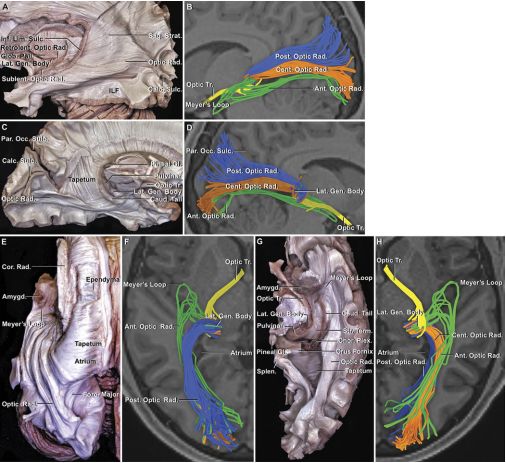

24.枕部经小脑幕入路对预防术后视野缺损的解剖学研究

Prevention of postoperative visual feld defect after the occipital transtentorial approach: anatomical study.

PMID: 29053071 DOI: 10.3171/2017.4.JNS162805

经枕小脑幕入路可以暴露幕上和幕下区域,处理涉及胼胝体压部、松果体、四叠体板和小脑上蚓部的病变,但该术式由于术中牵拉不当引起枕叶损伤进而导致术后视野缺损并发症。基于这一问题,本研究进行了对枕叶进行最小牵拉损伤、大脑的表面解剖、视辐射走形和经枕小脑幕入路显微解剖等方面的探讨。此外,辅助成角内镜可以很好暴露小脑中脑裂、上髓帆、小脑上脚。牵开枕叶下表面可以避免直接损伤距状裂周围皮质和视辐射。准确理解枕叶周围视辐射走形和血管的毗邻关系及小心牵开枕叶下表面有助于降低术后视野缺损的发生率。

【李信晓】